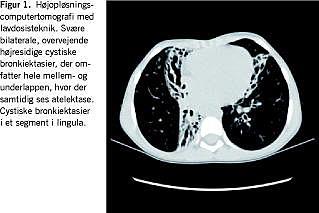

Røntgen af thorax viste bilaterale infiltrater og en højresidig mellem- og underlapsatelektase. Efterfølgende højopløsnings-computertomografi af thorax med stråleskånsom lavdosisteknik viste bilaterale omfattende cystiske bronkiektasier med kollaps af tilhørende lungeparenkym (Figur 1). Lungestetoskopien var med bilateral, spredt krepitation.